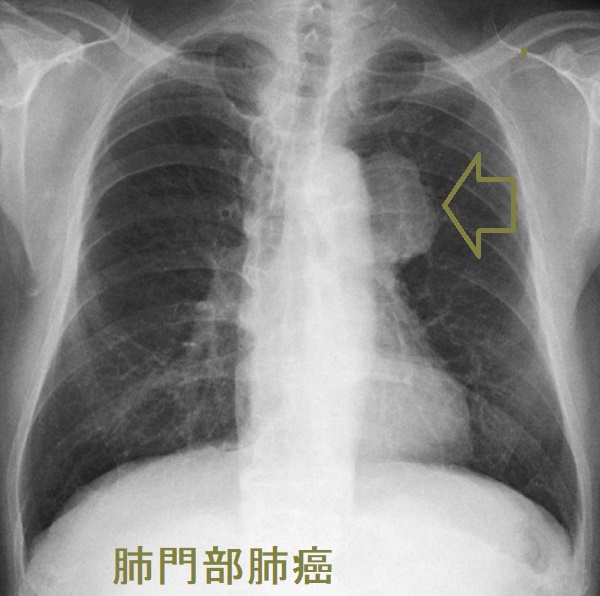

扁平上皮癌(肺門部肺癌、中心型肺癌)

肺門部肺癌 胸部X-p写真

肺門部肺癌(中心型肺癌) 胸部X-p写真

肺門部肺癌 縦隔リンパ節転移 反回神経浸潤

肺門部肺癌(中心型肺癌) 縦隔リンパ節転移 反回神経浸潤

肺門部肺癌(扁平上皮癌が多い)は、発熱や咳嗽(せき)がなく血痰のみで、胸部単純CTをしても異常を認めない場合があります。喀痰細胞診の検出感度は約40% にすぎないが、パパニコロウ(Papanicolaou)染色でオレンジGに染まる細胞があれば扁平上皮癌です。